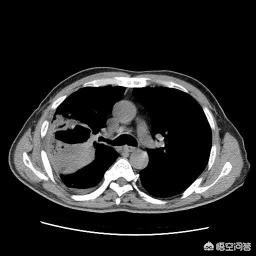

肺脓肿大部分为细菌感染所致,病原体包括若干种,常见的是厌氧菌,这一类细菌容易产生气体,并在肺组织中侵蚀周围组织形成坏死物排出体外,产生一个壁很厚带有液气平面的空洞灶,该细菌的治疗需要能够兼顾厌氧菌的抗生素治疗,比如哌拉西林、莫西沙星、甲硝唑等。